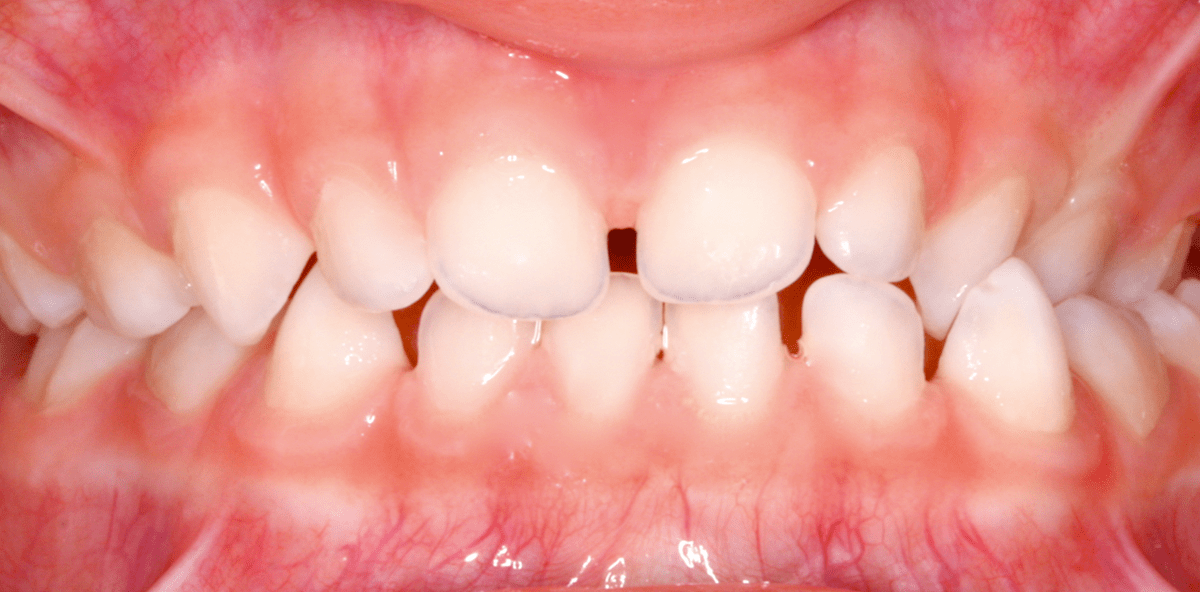

Die häufigste Anomalie des progenen Formenkreises ist in der Milchzahndentition und dem frühen Wechselgebiss der ein- oder beidseitige Kreuzbiss (Abb. 1). So macht der Kreuzbiss ca. 35 % der Frühbehandlungsfälle im Patientengut unserer KFO-Praxis aus. Kreuzbisse lassen sich gut mithilfe herausnehmbarer Behandlungsmittel, wie z.B. einer Dehnplatte mit seitlichen Aufbissen (Abb. 2), therapieren. Wenn sich andere Abweichungen wie z.B. offene Bisse hinzugesellen, besteht auch die Möglichkeit, den Kreuzbiss mittels GNE-Apparatur (ohne chirurgische Unterstützung) zu therapieren. Da die Geräte in der Regel gut von den ganz jungen Patienten getragen werden, liegt die Erfolgsrate (fünf Jahre nach der Kreuzbissüberstellung) bei über 90 Prozent. Die echte Progenie und Pseudoprogenie mit Bildung einer mesialen sagittalen Frontzahnstufe sind zu diesem Zeitpunkt der Dentition eher selten. Ihr Auftreten liegt um 1 Prozent der nach KIG zu behandelnden Patienten. In unserer kieferorthopädischen Praxis kommen hier neben aktiven herausnehmbaren Apparaturen vor allem der Funktionsregler FR III nach Fränkel zum Einsatz (Abb. 3), wobei sich diese frühe Behandlung über einen entsprechend längeren Zeitraum hinzieht.